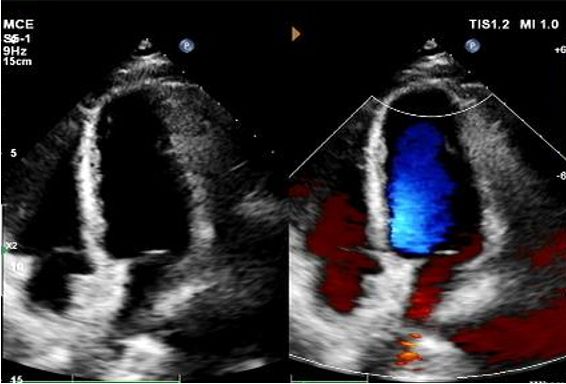

Tag 1 bis 9 Monate:

Kein Rest-Shunt beobachtet.

Allmähliche Verringerung der Geräte echogenität.